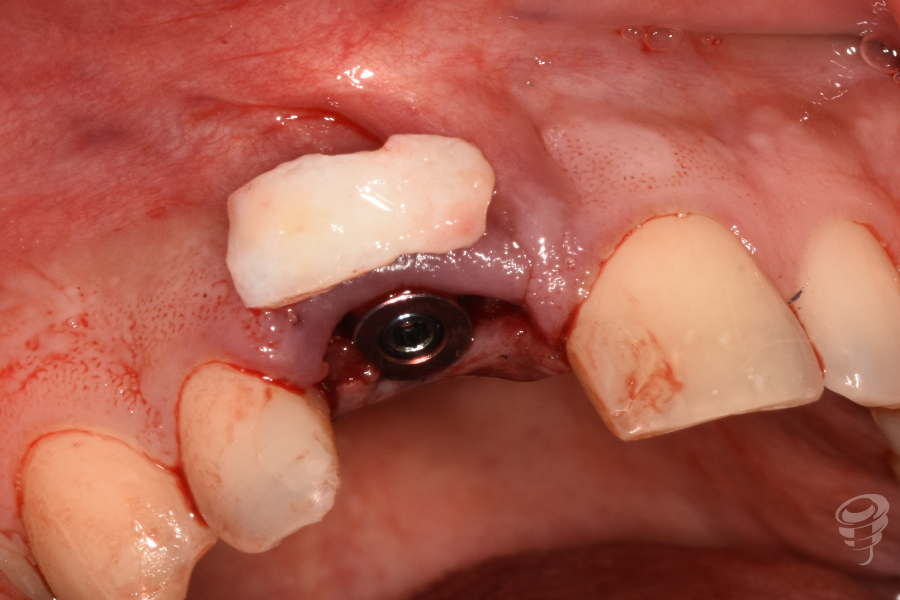

- Injerto óseo: Colocación de partículas xenogénicas y de fresado propio en el gap vestibular y coronal al implante. Injerto de tejido conectivo: Obtenido de la tuberosidad. Injerto subepitelial tunelizado vestibularmente al implante y suturado con Seralene 5-0.

- Provisionalización: Pilar titanio personalizado + corona provisional de resina acrílica (sin contacto oclusal), con la colocación de puntos suspensores para estabilizar la encía y márgenes gingivales.

Figura 22